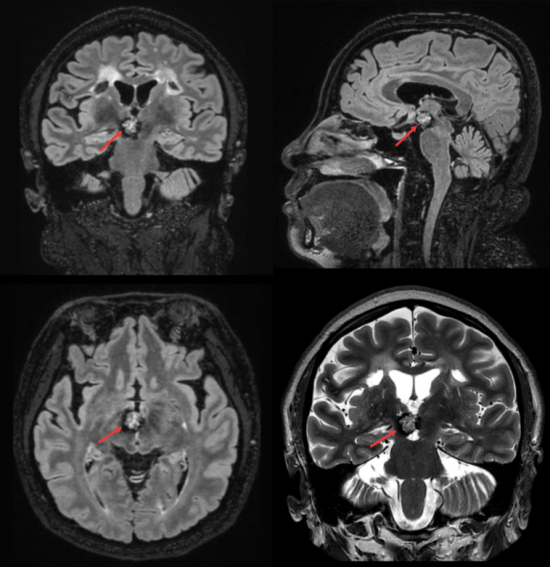

术前磁共振影像

患者王女士(化姓),今年51岁,因间断性头部胀痛前来就诊。经头部磁共振(MRI)检查,发现其右侧下丘脑、脑干区混杂信号,考虑海绵状血管瘤伴出血。孙家行教授介绍,下丘脑是大脑中的“核心中枢”,负责调节意识、内分泌、体温及感觉传导,周围密布着重要的神经纤维和核团。此处的病变传统开颅手术路径极长,损伤风险巨大,犹如“雷区排爆”,稍有不慎就可能导致患者昏迷、内分泌紊乱、感觉丧失、运动障碍等严重并发症,因此一直是神经外科领域难度最高的手术之一。